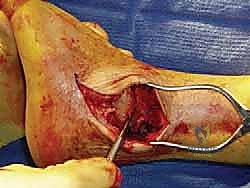

- الشق الجراحي الجانبي: يقوم الدكتور هطيف بعمل شق طولي دقيق على الجانب الخارجي للكاحل، مباشرة فوق عظم الشظية.

- قطع الشظية (Fibular Osteotomy): يتم قطع الجزء السفلي من عظم الشظية وإبعاده مؤقتاً. هذا الإجراء يفتح مفصل الكاحل تماماً أمام الجراح كالنافذة.

- تحضير الأسطح المفصلية (الخطوة الأهم): باستخدام أدوات جراحية دقيقة ومقاشط متخصصة، يتم إزالة كل الغضاريف التالفة المتبقية من أسفل عظم الساق (الظنبوب) وأعلى عظم الكاحل (السنخ). يتم كشط العظام حتى الوصول إلى طبقة العظم الإسفنجي النازف (Bleeding Subchondral Bone). هذا النزيف ضروري جداً لأنه يحتوي على الخلايا الجذعية وعوامل النمو التي ستبني العظم الجديد.